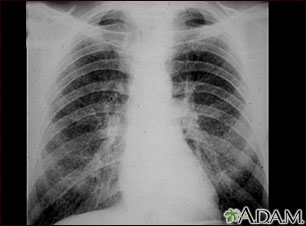

Esta radiografía de tórax muestra la neumoconiosis del minero etapa II (CWP, por sus siglas en inglés). A ambos lados del pulmón hay áreas difusas, pequeñas y claras. Otras enfermedades que pueden explicar estos hallazgos en una radiografía son, entre otras: la silicosis simple, la tuberculosis diseminada, cáncer metastásico de pulmón y otras enfermedades pulmonares infiltrativas y difusas.